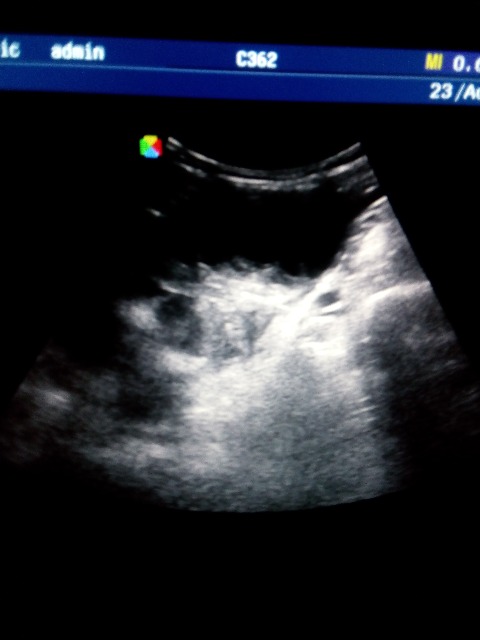

Подскажите что это может быть, лоцируется на уровне дна матки, справа и слева, больше слева, у женщины c-r шейки матки, проходит обследование брюшной полости перед лечением в онкодиспансере, недавно делали УЗИ малого таза, без патологии, никаких образований, кист не находили, жалоб нет. Думаю расширенные петли кишечника, заполненные жидким содержимым, перистальтики не увидела, если это они то какая может быть причина, и как то нужно это в протоколе и заключении отразить?

По фото можно подумать и про яичники и по некоторым фото про петли. Нужно видео!

Форма вытянутая, общей капсулы нет и с двух сторон, наверное кишечник, просто я его таким не видела еще.. ну а если абстрагироваться от этого случая, то что вообще писать в заключении в случае расширенных и заполненных жидкостью петель, если больной амбулаторный планово пришел? какие рекомендации?